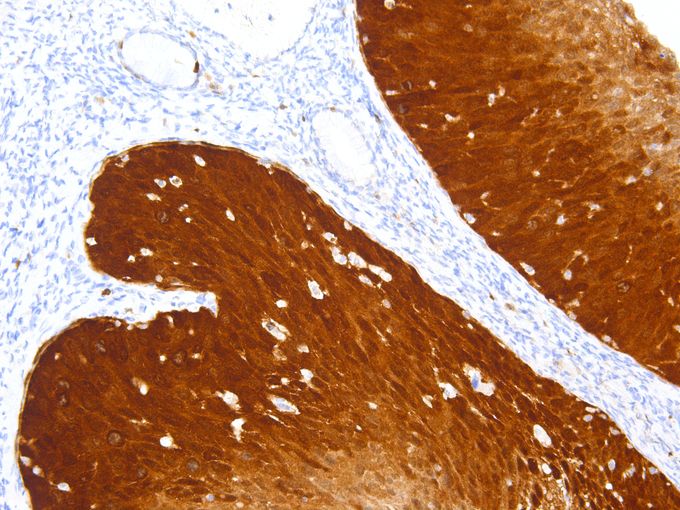

IHC-P analysis of human colon tissue using GTX57189 CDKN2A / p16INK4a antibody [IHC016]